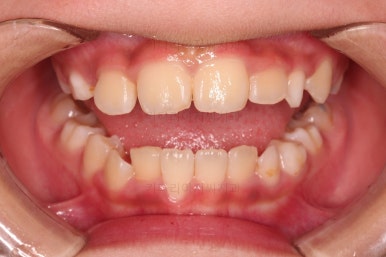

1. 초진

초진 시 입안의 모습입니다.

가장 눈에 띄는 건, 아랫니가 윗니보다 앞에 나와있는 부정교합인데요.

부산어린이교정 초진 시 얼굴 모습인데요.

아랫 입술 부위가 앞으로 많이 나와 있어 주걱턱의 느낌을 주고요.

웃거나 말할 때 아래 앞니가 앞에 튀어나와 있어 심미적으로도 좋지 못하죠.

반대교합이 주로 좌측 앞니쪽에서 있다보니 해당 부위로 아래턱이 밀리면서 앞모습에서 비대칭도 보입니다.